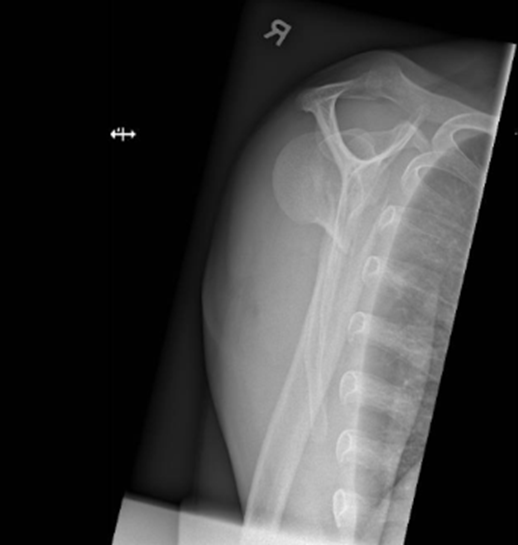

The patient underwent open reduction internal fixation (ORIF) on post-injury day 11. Following a deltopectoral approach and biceps tenodesis, the 4-part PHFD was seen. The humeral head was posteriorly dislocated and impacted upon the posterior glenoid with a nondisplaced head split. The greater tuberosity fragment was identified with an intact supraspinatus However there was an avulsion of the subscapularis off the lesser tuberosity. The humeral head was reduced with judicious soft tissue management and assessed in-situ to prevent secondary injury and ischemia. The articular block was secured with 2 headless compression screws. The neck-shaft angle was restored using plate-assisted reduction and an angular stable construct was achieved with an anatomical locking compression plate (Synthes PHILOSTM). To prevent varus malunion, the height of the plate was determined on fluoroscopy (Image 2) to enable the inferomedial ‘kickstand’ screw [31]. The medial calcar was reduced and cerclaged to the plate for bony apposition and increased fixation strength. Cement augmentation (Stryker Hydroset) was performed. Transosseous repair of the Subscapularis was done with closure of the rotator interval.

Image 2: Intraoperative fluoroscopy demonstrating satisfactory anatomical reduction of the 4-part proximal humeral posterior fracture-dislocation.